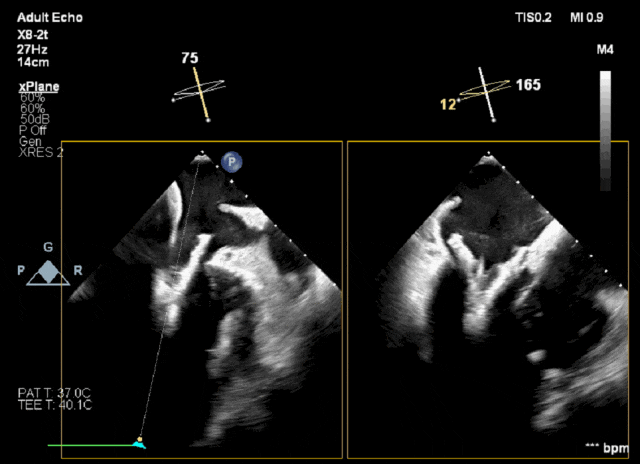

手术采用左侧第五肋间微创切口入路,超声引导下经心尖将导丝置入左房,送入瓣膜输送系统,经过一系列超声定位后逐渐释放瓣膜。整个释放过程平稳,瓣膜锚定位置精准且未发生位移,瓣架张开完整,与瓣环贴合良好无瓣周漏,人工二尖瓣瓣叶对合形态完好无反流,左室流出道无梗阻,无传导阻滞。术中无出血,无输血,术后患者安全返回监护室。

TMVR术中

术后一周患者顺利出院。出院前心超结果:经导管二尖瓣植入术后,人工瓣膜支架锚定良好,瓣膜功能良好,瓣叶开放正常,连续多普勒估测瓣口面积为3.79cm²,估测瓣口前向峰值压差2mmHg,平均压差1mmHg,瓣叶关闭形态未见异常,彩色多普勒未测出二尖瓣反流,左心室流出道通畅,流出道峰值流速0.75m/s。